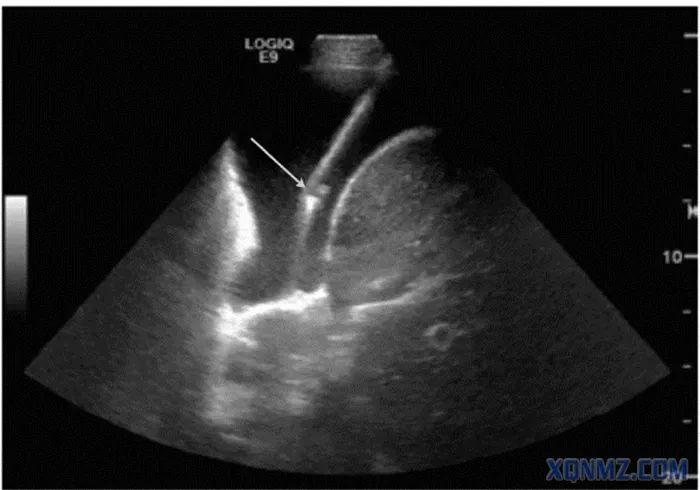

超声引导下胸腔穿刺术

(实时超声下穿刺可见大部分穿刺针及针尖显示(箭头所示))

胸腔积液是急诊常见的临床情况,可以作为各类疾病的伴发状态,包括肿瘤性疾病、感染性疾病、炎症疾病和器官功能不全等。胸腔积液穿刺抽吸或置管引流可诊断和/或缓解患者的呼吸系统症状;也可进行胸腔冲洗、注射药物治疗等。选择3.5~5.0 MHz腹部超声探头,全面检查胸腔积液情况及分布,穿刺应选无回声区较深,并远离心肺等重要器官的部位,针头在超声屏幕上显示为无回声区中的强回声点。【2】